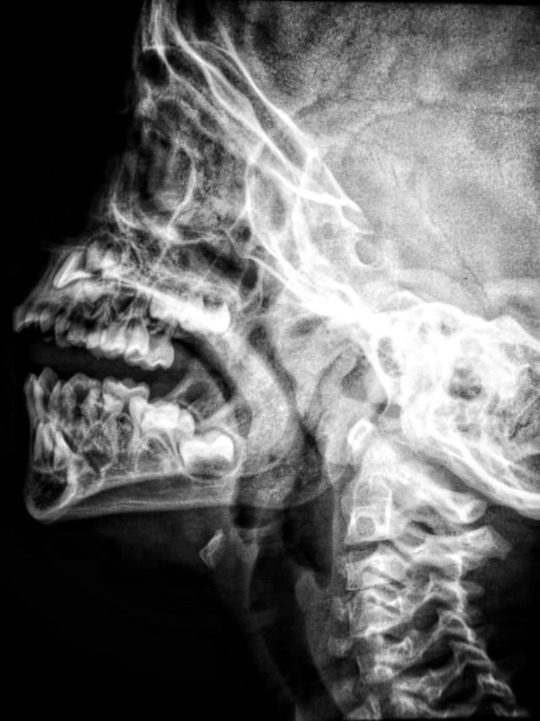

もやもや病は、脳の血管に起きる病気でもやもや血管がみられる

もやもや病は、脳の血管に起きる病気で、一時的な手足の麻痺や言語障害が起きます。

もやもや病を発症すると、脳の底にもやもや血管がみられます。もやもや血管は、内頚動脈の終末部が細くなることで脳の血液が足りなくなり、血液を補うために脳の血管が広がりできた血管です。

脳の血管の塞がりは、発症した時と状態が何十年も同じ状態である人のいれば、少しずつ症状が進んでいく人もいます。そのため、MRIなどを定期的に受けることが大事です。